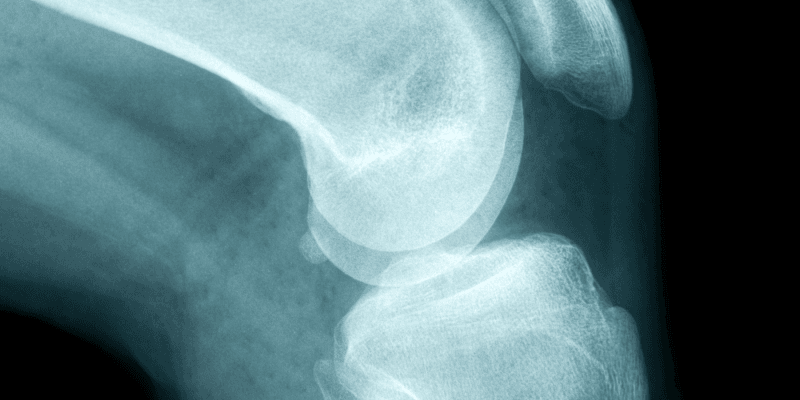

Biological tissues are amazing materials. Over the years, our biological tissues mature and change so they can provide exactly what’s needed for their individual function, like how elastic cartilage can resist compression but cushion our joints at the same time. As mere mortals, it’s tough to fabricate synthetic replacements that mimic what our biological tissues are capable of, but 3D printing can help. A team of scientists from University of Colorado Denver (CU Denver) have succeeded in creating a 3D printing material that can replicate the properties of human tissue, and published their results in a paper titled “Liquid‐Crystal‐Elastomer‐Based Dissipative Structures by Digital Light Processing 3D Printing.”

They created a liquid crystal resin, similar to honey, that generates new bonds in the form of photopolymer layers when cured with ultraviolet light. The cured resin creates a compliant elastomer that’s both soft and strong, and begins to mimic cartilage when it’s 3D printed in a lattice structure.

In addition to shock-absorbing football helmets, these DLP printed LCE structures could have many other applications as well, such as small biomedical implants for toes and spinal devices.

“The spine is full of challenges and it’s a hard problem to solve. People have tried making synthetic spinal tissue discs and they haven’t done a good job of it,” Yakacki said. “With 3D printing, and the high resolution we’ve gotten from it, you can match a person’s anatomy exactly. One day, we may be able to grow cells to fix the spine, but for now, we can take a step forward with the next generation of materials. That’s where we’d like to go.”